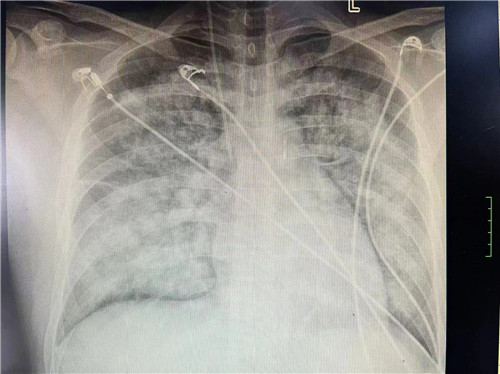

心内科主任潘宏伟教授了解情况后,与家属反复沟通,家属最终同意ECMO治疗。2月3日,心血管内科一病区何晋主任医师、张艳护士长带领的医护团队成功为小王置入ECMO。ECMO置入后,小王明显感觉自己情况有所好转,但CCU重症医护团队并不敢掉以轻心,安排专医专护管理病情,最终小王全程未出现感染、血栓、出血等ECMO合并症,情况恢复稳定,于2月28日顺利出院。